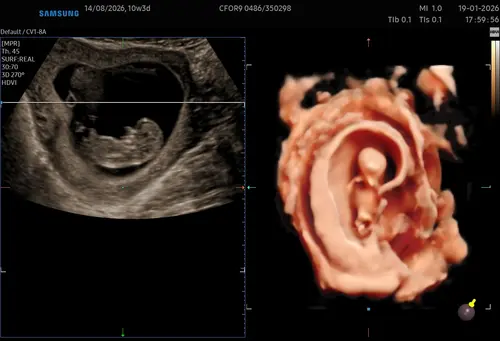

10weken4 dagen😍

Oh dat is echt al een mensje! Ik ben nu 10+2 weken en moet nog 2 weken wachten op mijn volgende echo 🤩